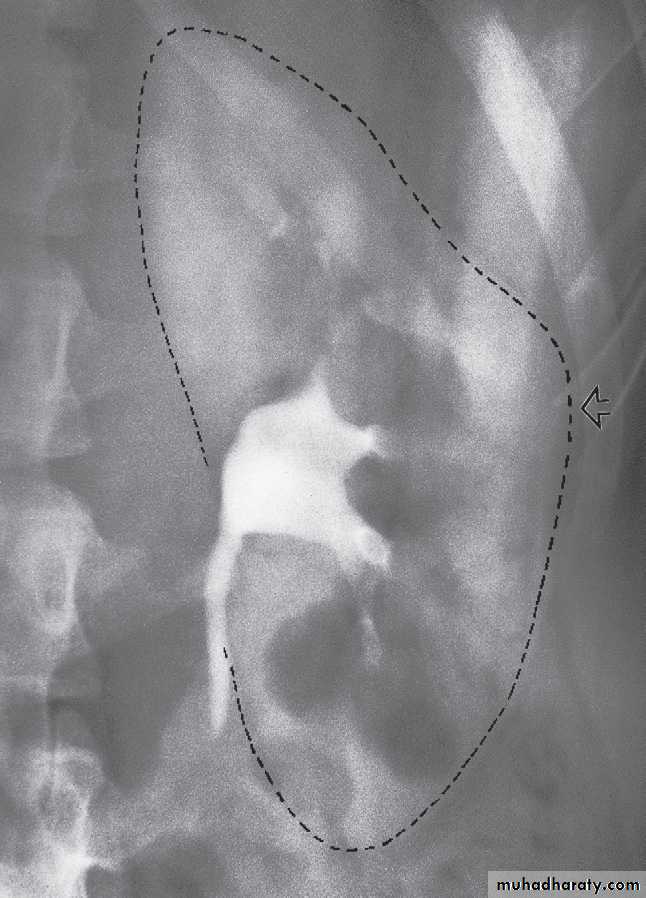

1 .Check that the kidneys are in their normal positions . The left kidney is usually higher than the right.2 .Identify the whole of both renal outlines. If any indentations or bulges are present they must be explained.

• Local bulges of the renal outline.

The normal renal pelvis and pelvi-ureteric junction are funnel shaped. The ureters are usually seen in only part of their length on any one film of IVU because of obliteration of the lumen by peristalsis.Congenital variations of the renal collecting system are relatively common .